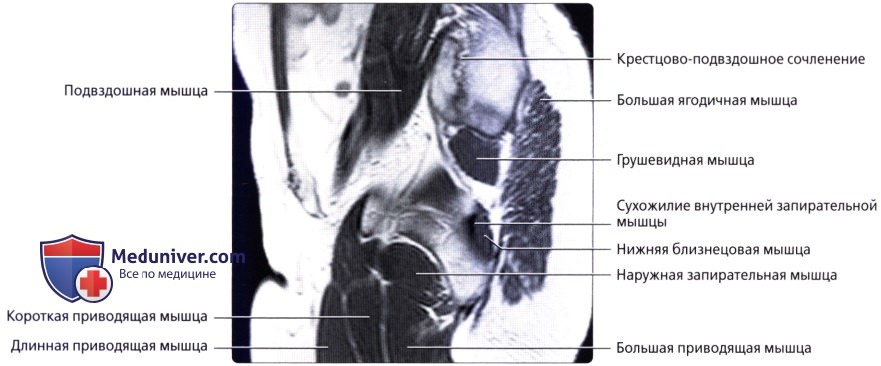

Запирательный бугорок

Запирательный бугорок 109 фотографий